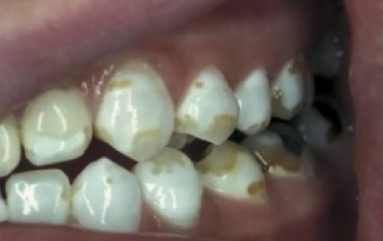

Tetracyclin Stain (TC stain)

Betel nuts stain

Fluorosis